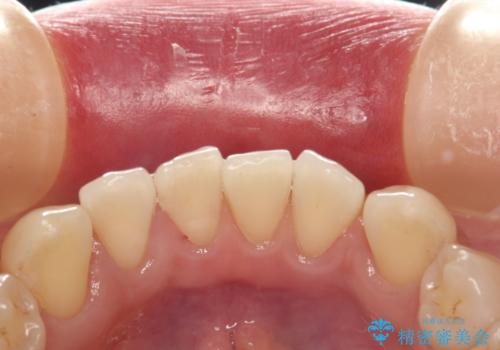

前歯の着色をPMTCできれいに除去

- 前歯の着色が気になるとのことで来院されました。PMTC30分コースを行いました。

そのため、PMTC(歯科医院にて、専門的なクリーニング)を定期的に行うことで、着色が付きにくい歯質の強化、健康で審美的にも美しい口腔内環境を維持すことにつながります。